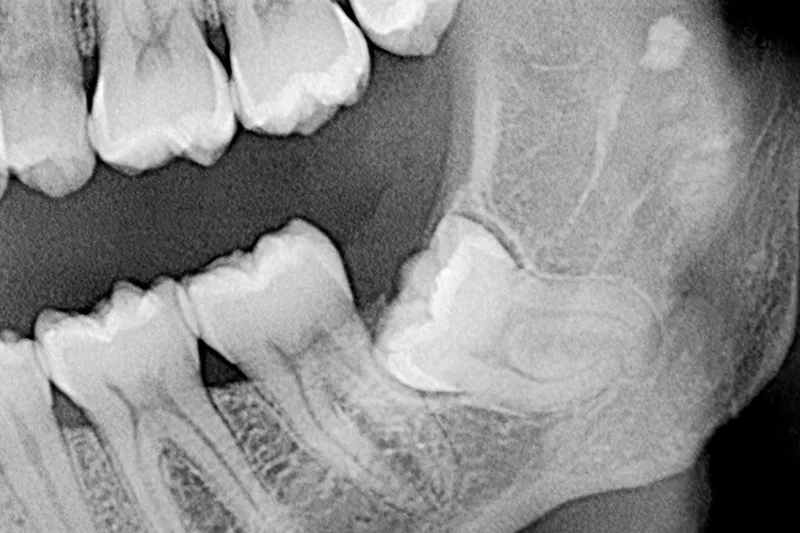

Radiologisk undersøgelse før kirurgisk fjernelse af mandiblens tredjemolar

Det er lege artis at foretage en røntgenundersøgelse forud for kirurgisk fjernelse af mandiblens tredjemolar (M3 inf.), og intraoral periapikal eller panoramaoptagelse anses for førstevalg, mens Cone Beam Computed Tomografi (CBCT) kan anvendes i særlige patienttilfælde, hvor der foreligger et ønske om en mere detaljeret radiologisk undersøgelse af relation mellem canalis mandibulae og rodkomplekset af M3 inf. samt eventuelt omkringliggende sygdom. Imidlertid er det vist, at radiologiske fund på CBCT hverken ændrer på behandlingen af M3 inf. eller på patientens postoperative forløb, herunder forekomsten af neurosensoriske forstyrrelser sv.t. n. alveolaris inferior (NAI). Derudover er det vanskeligt at identificere, hvilke radiologiske tegn der kan benyttes som prædiktorer for en neurosensorisk forstyrrelse sv.t. NAI. De klassiske syv panoramategn er således ikke længere valide. Nyere forskningsresultater på et højere evidensniveau har vist, at tilfælde, hvor M3 inf.’s rødder strækker sig kaudalt for den nedre begrænsning af c. mandibulae, er forbundet med en øget forekomst af permanent neurosensorisk forstyrrelse. Den generelle anbefaling vedrørende radiologisk undersøgelse før kirurgisk fjernelse af M3 inf. er derfor, at 2D radiologisk undersøgelse er tilstrækkeligt i hovedparten af de patienttilfælde, hvor M3 inf. skal fjernes.

Den kliniske undersøgelse skal suppleres af en sufficient radiologisk undersøgelse i forbindelse med diagnostik og behandlingsplanlægning før kirurgisk fjernelse af mandiblens tredjemolar. Valg af radiologisk metode beror på, hvilken information behandleren finder nødvendig for at kunne lave en fyldestgørende klinisk og radiologisk undersøgelse, hvor det er nødvendigt, at mandiblens tredjemolar samt relation til nærliggende anatomiske strukturer belyses sufficient. Denne beslutning bør foretages på et evidensbaseret grundlag, hvor også viden om stråledosis og økonomiske forhold bliver taget i betragtning særlig ift. overvejelsen omkring CBCT.